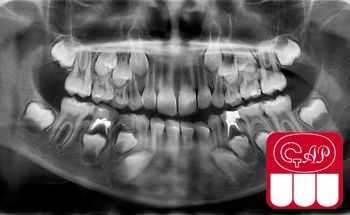

Материал и методы Нами была проанализирована 71 ортопантомограмма смешанного прикуса детей в возрасте от 6 до 13 лет, обследованных в 2001 - 2004 гг. по ортодонтическим показаниям. В зубной формуле каждого ребенка отмечали степень прорезывания коронки зуба (СПК) и степень формирования корня зуба (СФК). Напомним, что внечелюстной этап прорезывания коронки зуба имеет три степени: 1-я степень - появление над десной режущего края или бугра коронки; 2-я степень - прорезывание коронки до уровня экватора, 3-я степень - прорезывание всей коронки полностью [2].

В формировании корня зуба нами также были выделены три степени, соответствующие периодам его созревания: 1-я степень - рост корня в длину; 2-я степень - корень с несформированной верхушкой в виде раструба; 3-я степень - корень с незакрытой верхушкой.

Результаты и их обсуждение При сопоставлении СПК и СФК одного и того же зуба было выявлено, что 89 % зубов имеют одинаковое значение СПК и СФК. Из 11% зубов с различными значениями СПК и СФК у 78 % зубов СФК на одну единицу опережает СПК. Причем, у тех зубов, диапазон прорезывания которых меньше (у резцов и первых моляров), а, следовательно, и темпы их прорезывания выше, практически нет разницы между СПК и СФК [4].

Выводы Была выявлена сильная положительная корреляционная связь (коэффициент корреляции равен +0,99) между степенью прорезывания коронки зуба (выявляемого клинически во время осмотра зуба) и степенью формирования корня зуба (выявляемого рентгенологически). Следовательно, если коронка зуба имеет, к примеру, вторую степень прорезывания, то ее корень находится на 2-й или даже 3-ей степени своего формирования. Этот факт, несомненно, должен приниматься во внимание при планировании эндодонтического и ортодонтического лечения постоянных зубов, особенно при нежелательности или невозможности проведения рентгенологического исследования.